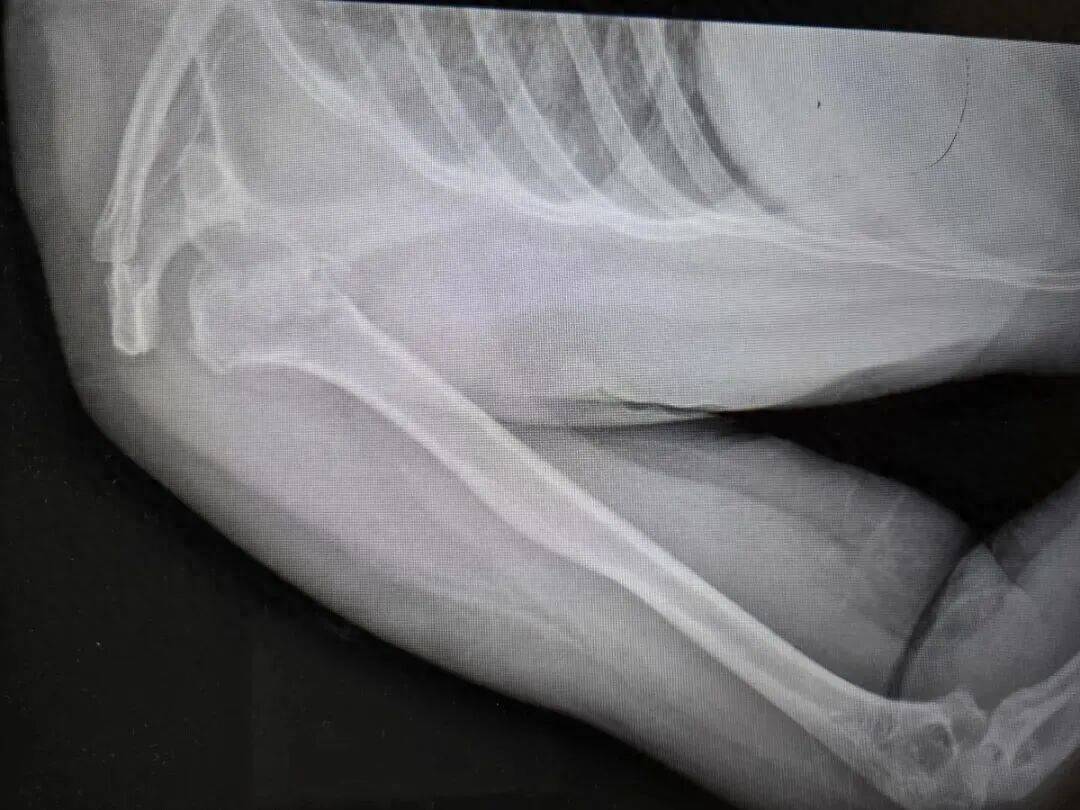

近日,河南50岁的张大姐在睡梦中突发肩膀粉碎性骨折,骨头碎裂成七八块,其丈夫表示,事发时张大姐全程均躺在床上,未受外部撞击。

患者被送往河南省人民医院后,该院创伤骨科主任刘涛坦言,初见病情时十分意外,这类严重骨折通常由高空坠落、车祸撞击等高能外力导致。随后,创伤骨科与神经内科联合会诊检查,最终查明病因是张大姐癫痫发作,上肢猛烈抽搐挥舞引发骨折。

针对张大姐的病情,医院诊疗小组制定了专属治疗方案,手术中不仅将劈裂的肱骨头、后脱位等四大部分共七八块碎裂骨头按原貌完整复位,还对受损肌腱进行了修复,并为骨骼塌陷部位填充支撑骨。